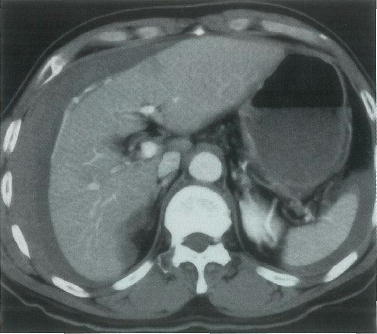

61歳の男性。黒色便を主訴に来院した。1年前に肝細胞癌と診断され,ラジオ波焼灼を受けた。血液所見:赤血球 220万,Hb 7.5g/dl,白血球 2800,血小板 7万,プロトロンビン時間 65%(基準 80~120)。血清生化学所見:アルブミン 3.3g/dl,総ビリルビン 1.8mg/dl,AST 72単位,ALT 65単位。腹部造影CTを別に示す。

治療として適切なのはどれか。

正解 c

診断 胃静脈瘤出血